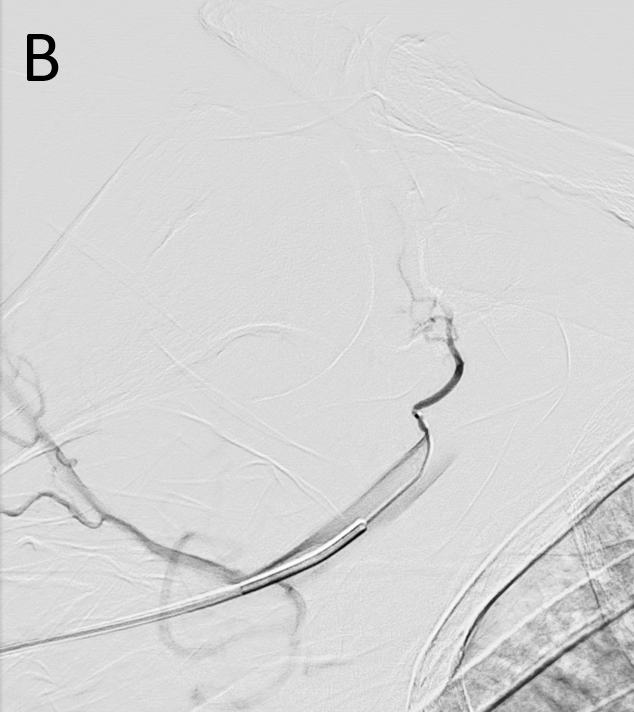

The procedure is typically performed on an outpatient basis, with a low complication rate and minimal recovery time. An arteriography of the upper or lower limb is performed depending on the joint to be treated. A 3F to 6F catheter is usually employed and the use of small microcatheters, from 1.7F to 1.9F, is recommended. The target of the embolization is the disappearance of the hypervascularized areas called “blush areas” (Figures 1 and 2), for which different types of materials, spheres, imipenem/cilastatin or lipiodol mixed with contrast can be used as embolic agents [10–12].

Figure 2. A. Super-selective angiography with the microcatheter from the coracoid artery (white arrow). Blush enhancement of the rotator interval (circle). B. The final angiography confirms the patency of the coracoid artery and the disappearance of the initial arterial blush.